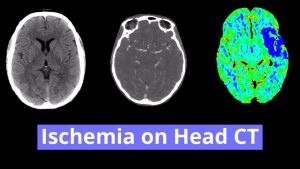

- Areas of hypoattenuation in the posterior limb of the right internal capsule, inferior left thalamus, right hemipons, and right cerebellar hemisphere

Small vessel infarcts involving the posterior limb of the right internal capsule, inferior left thalamus, right hemipons, and right cerebellar hemisphere, which are age-indeterminate in the absence of prior imaging for comparison. Consider MRI for further evaluation if there is clinical concern for acute infarct.